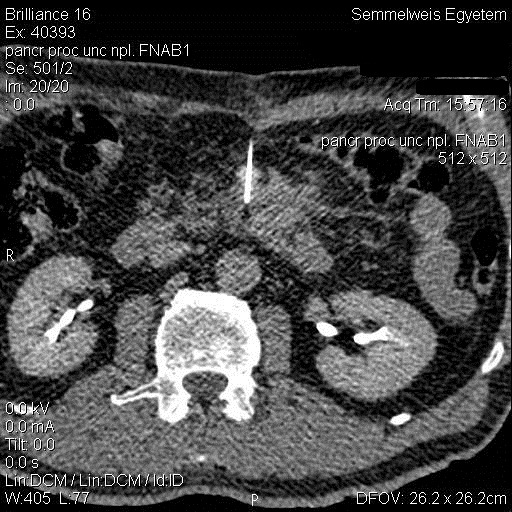

19.2.2.2. CT guided biopsy

Ideal method if the lesion is located either in the chest (figure 5.), mediastinum, retroperitoneum (figure 6.) or the pelvis.

Figure 6. – CT guided pancreatic biopsy